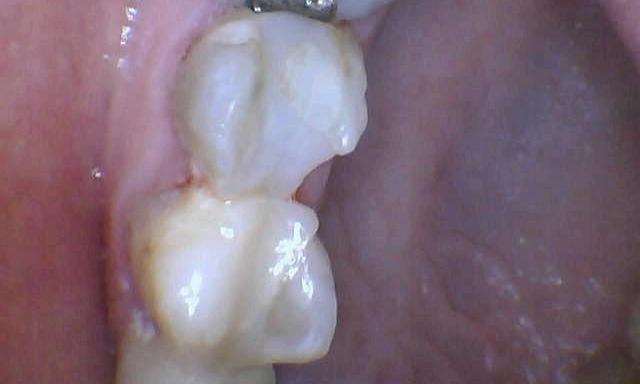

Same Day Crown

A same day crown completed to restore a cracked molar with recurrent decay.

After